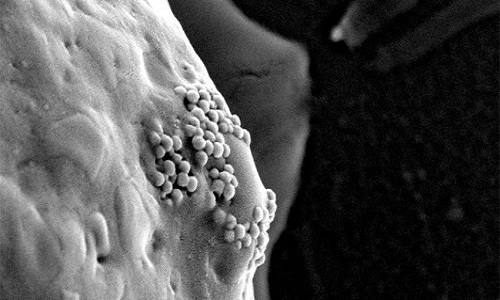

Khối u ung thư thường có các mạch máu rò rỉ. Khi hạt nano vàng được tiêm vào mạch máu, chúng có xu hướng thấm qua các lỗ mạch rò rỉ này và tụ xung quanh khối u. Những tế bào ung thư khi phát triển thường "nuốt" các hạt nano. Sau khi lọt vào bên trong tế bào ung thư, các hạt nano này đóng vai trò như con ngựa thành Troy. Khi các nhà nghiên cứu cho các nguyên tử vàng tương tác với ánh sáng laser hồng ngoại, một loại sóng điện từ có thể đi xuyên qua các mô, hạt nano sẽ bị nóng lên và đốt cháy các tế bào ung thư.

Nhóm nghiên cứu gắn hạt nano vàng vào các kháng thể protein miễn dịch. Kháng thể protein sẽ tiếp xúc với thụ thể trên bề mặt tế bào vảy, cho phép hạt nano vàng bám vào xung quanh các tế bào ung thư một cánh nhanh chóng. Khi đó, thay vì đốt nóng liên tục bằng tia laser, các nhà khoa học chỉ cần dùng tia laser dạng xung siêu ngắn để đốt nóng tế bào ung thư. Laser hồng ngoại xung siêu ngắn có năng lượng thấp, không gây hại cho các tế bào khỏe mạnh.

Phương pháp này ngăn cản sức nóng lan sang các mô khỏe xung quanh tế bào ung thư, đồng thời sinh ra nhiệt độ cao hơn ở nơi có hạt nano vàng tập trung thành cụm lớn. Nhiệt độ cao làm bốc hơi các phân tử nước gần đó, tạo ra bong bóng siêu nhỏ. Những bong bóng này nhanh chóng lan rộng và nổ tung, phá vỡ các tế bào ung thư. Theo Lapotko, điểm mấu chốt là các cụm hạt nano vàng tạo ra bong bóng siêu nhỏ trong các tế bào ung thư mà không phải tế bào thường.